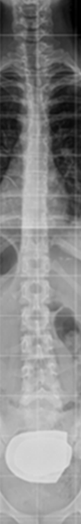

Conseguida una proyección correcta, vista de frente, la columna vertebral sana, será recta. Los pedículos vertebrales se verán en posición simétrica respecto al cuerpo vertebral donde asientan, con las apófisis espinosas en el centro entre ambos.

La línea plomada (línea imaginaria vertical que va de la apófisis espinosa de la última vértebra cervical a la correspondiente de la última vértebra lumbar) pasa por todas las espinosas. Sin embargo, Cobb, tal como apunta en su libro Staheli, reconoce variantes de hasta 10° como situaciones en las que no se ha comprobado que produzcan inestabilidad de ningún tipo en el niño ni en el adulto1.

Las costillas se visualizan simétricas con inclinación curva y espacio intercostal simétrico en los dos hemitórax.